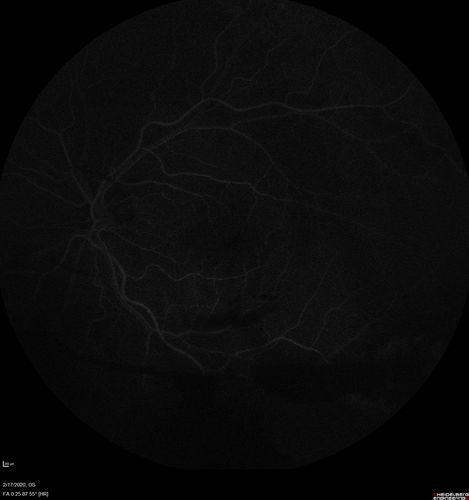

PDR and Vitreous Hemorrhage - High Risk Left Eye - Low Risk Right Eye

50 year old man with type I diabetes mellitus for 26 years. New Vitreous Hemorrhage in the left eye. Both eyes have NVE. Both also have foveal hypoplasia

Vitreous Hemorrhage and Proliferative Diabetic Retinopathy - Low risk right eye - High Risk Left Eye - Also Fovea Plana